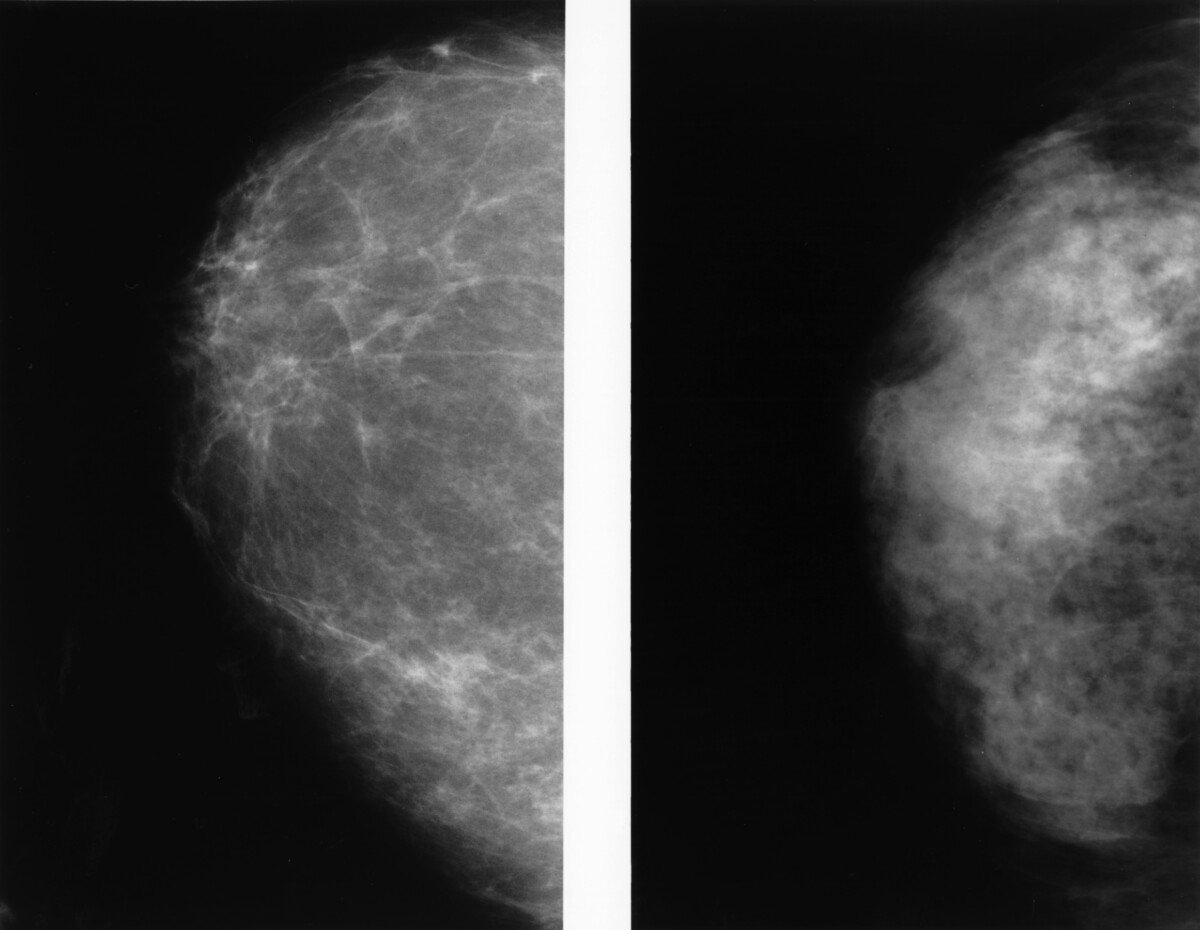

From www.researchgate.net

A mammogram of the left breast showed a left breast lesion with Painful Breast Lump Biopsy fine needle aspiration, core needle biopsy, and surgical (open) biopsy are the most common types of breast biopsies. for a few days after the biopsy, your breast or chest area may feel sore and bruised. a breast biopsy might be recommended if you have a suspicious area in your breast, such as a breast lump or other. Painful Breast Lump Biopsy.